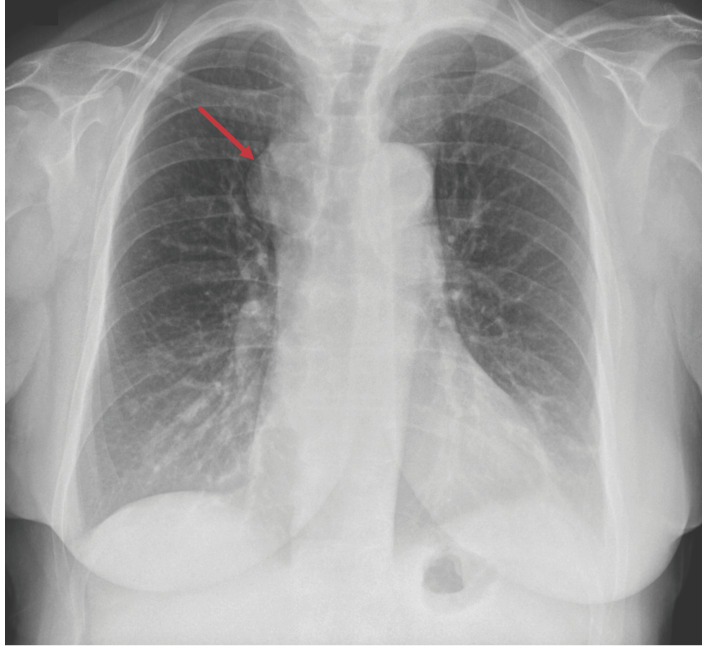

Intrathoracic goiters can be classified as primary or secondary. Primary intrathoracic goiters are characterized by the absence of any anatomical connection with the cervical thyroid gland, in contrast to secondary intrathoracic goiters. A rare variant, termed mixed or combined intrathoracic goiter, involves the synchronous presence of both primary and secondary components within the thoracic cavity. Given the rarity and the diagnostic challenges associated with these conditions, we report the case of a patient who presented with a multinodular goiter and a separate right paratracheal mediastinal mass. The latter was identified as ectopic thyroid tissue, consistent with a primary intrathoracic goiter. We describe the diagnostic approach used to differentiate the mediastinal mass from other thoracic pathologies, as well as the successful surgical management performed via a minimally invasive technique and facilitated a rapid and uneventful postoperative recovery.